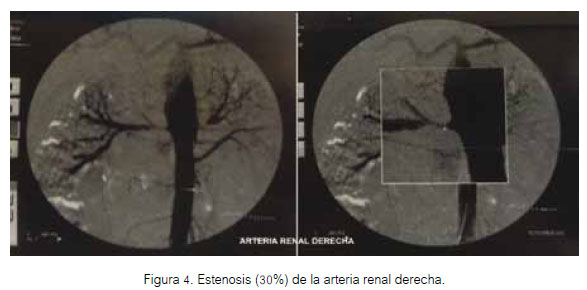

A las cinco semanas de su ingreso, se realizó arteriografía renal, que se observa en las figuras 3 y 4.